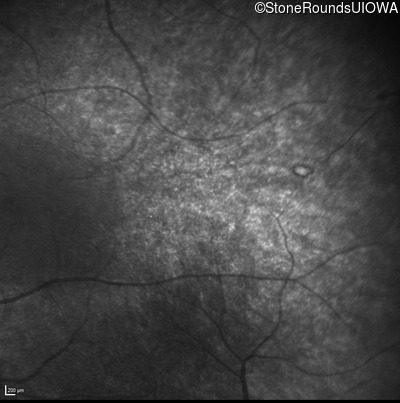

Infrared Fundus Photograph - Right - No Light Perception

Exemplar